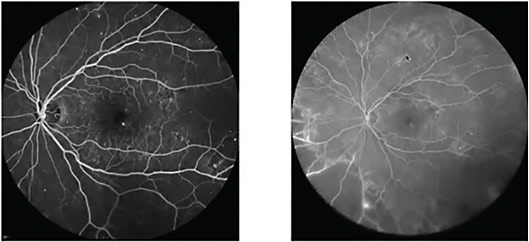

Although it can be identified clinically, ischemic maculopathy-associated DME (blunt foveal reflex with ghost vessels, Figure 1) can be difficult to quantify clinically, and you need FFA for this purpose. Focal laser (prompt vs. rescue) can be then considered based on the clinical scenario. Focal circinate lesions that are leaking on FFA can also be targeted using focal laser. It is important to consider that an ischemic macula leads to a massive release of VEGF, which might worsen DME and causes its recurrence.